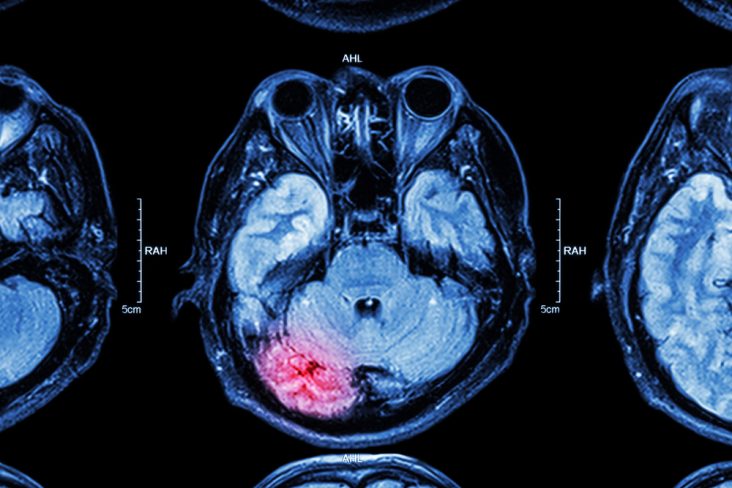

Seven years ago I had a major stroke, which left me with lifelong disability down my left side. I spent four months in hospital rehabilitation, building up my strength, learning to walk again and preparing to re-enter the world.

After travelling the globe for close to a decade after retirement, she sadly had a stroke in 2016. Regrettably, this was rapidly followed by another more serious brain injury, caused by an admitted failure by the hospital to give her blood thinners in the weeks after her stroke. A blood clot formed, depriving her brain of oxygen. After life-saving surgery, Mum woke up in the ICU a very different person to what she was before. The tour de force of a person that everyone still speaks of with pride and fondness had sadly disappeared.